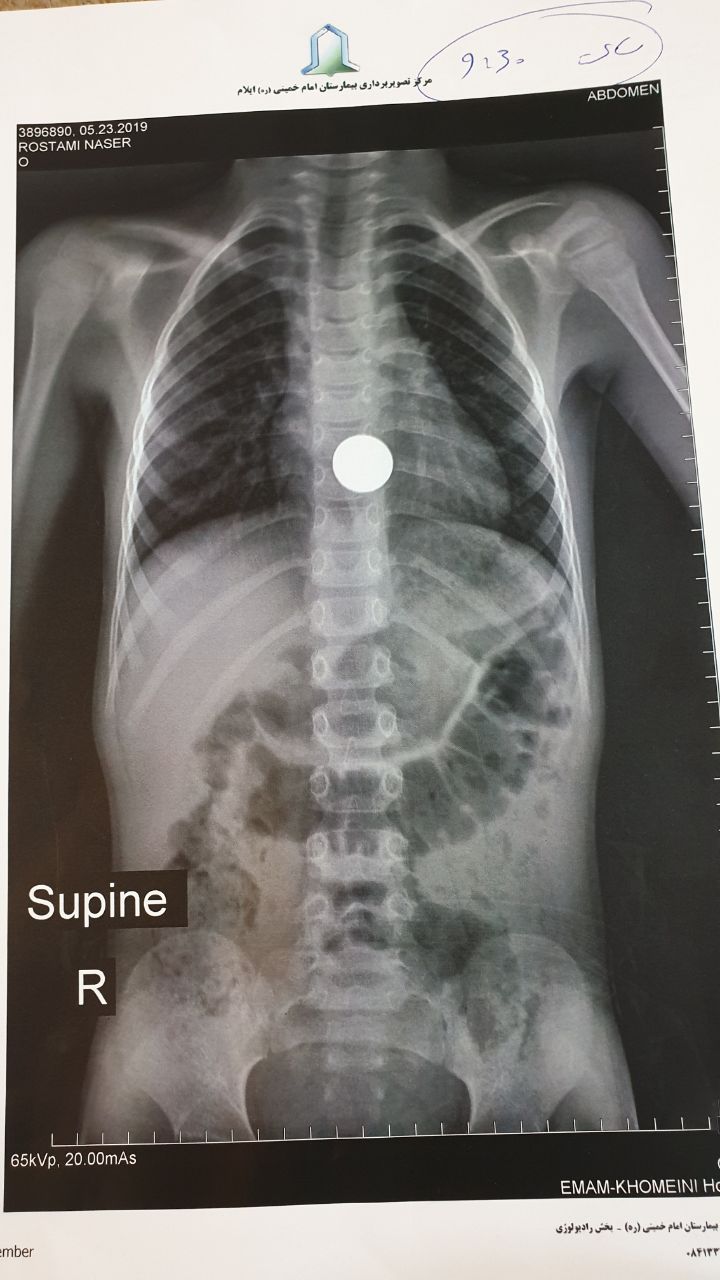

بازتاب ایلام- همانطور که در تصویر مشاهده می کنید، یک پسربچه اهل چوار، به دلیل قورت دادن یک سکه دچار مشکل حاد تنفسی شده و پس از اعزام به اورژانس بیمارستان امام خمینی(ره) به دلیل نبود تجهیزات و دستگاه ویژه نوزادان برای این منظور(آندوسکوپی)؛ خانواده دردمندش مجبور شده اند این پسربچه را با این اوضاع بحرانی و با هزاران دلهره، به استان کرمانشاه اعزام کنند تا شاید فرجی حاصل شود و از مرگ حتمی نجات یابد.!